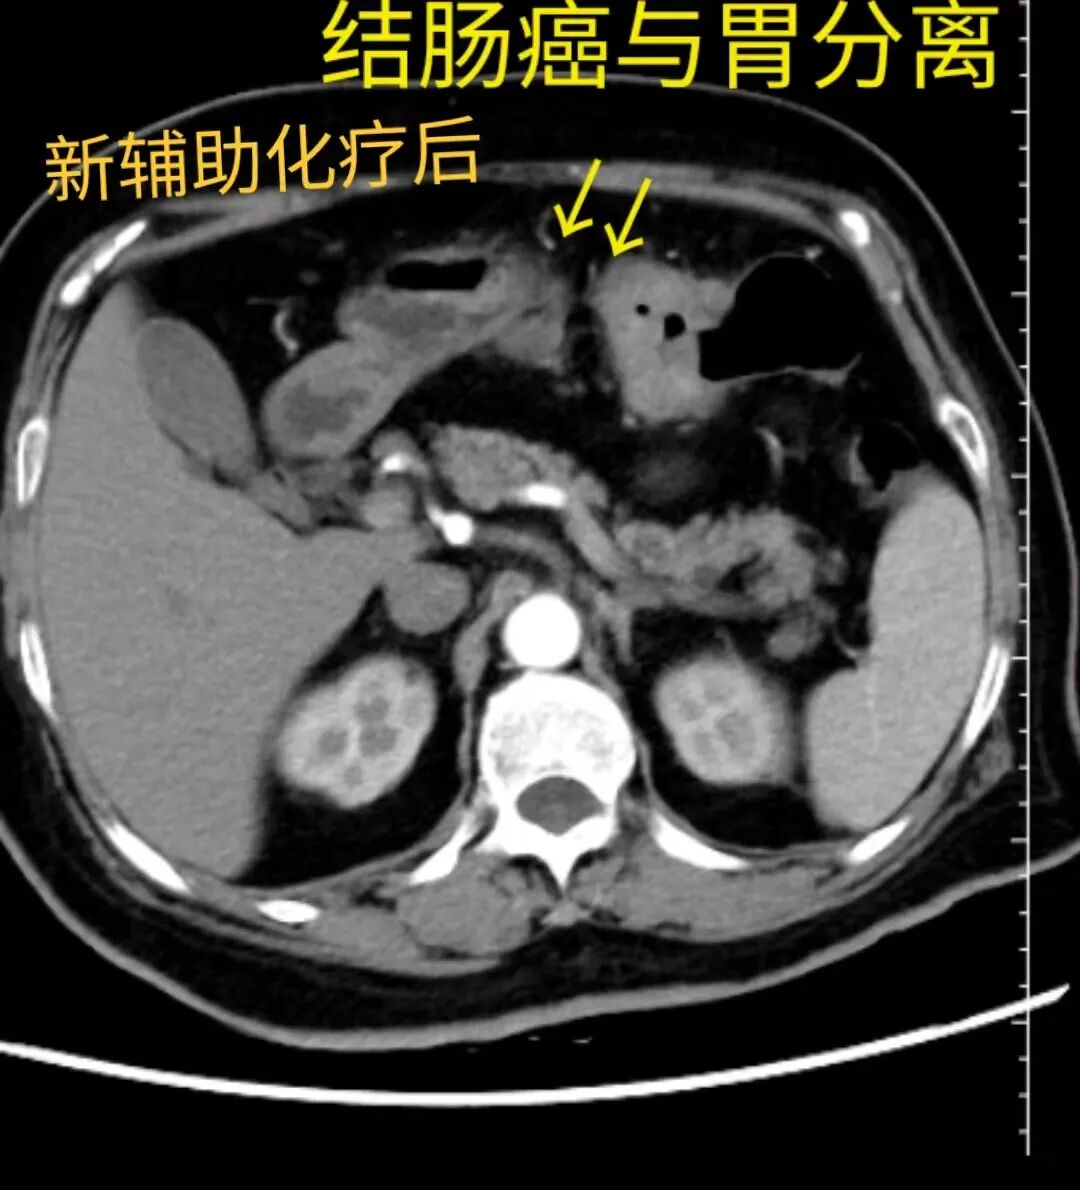

期间,患者每两周到门诊复诊,监测患者的体重,营养状态,血液学项目以及运动能力等情况,随着新辅助化疗的实施和功能锻炼,患者状态日益好转,在经历了新辅助治疗三个周期后,也就是就诊两个多月后,迎来了评估时刻。此时,患者体重无减轻,每日能步行4000-6000步,自我感觉状态良好。尤其是增强CT复查评估,效果非常好,经过三次化疗,结肠癌明显缩小,与胃壁的侵犯分离,手术不必再进行部分胃的切除。